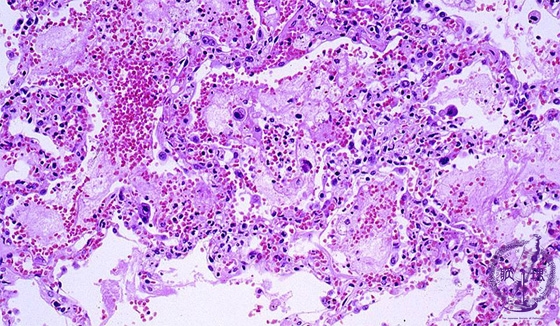

- ★(8)Viral pneumonia (cytomegalovirus inclusion body pneumonia)

Microscopic view (HE stain, low power view): The interstitial pneumonia pattern is shown. In this case, there are infiltrating neutrophils, necrosis, hemorrhage and scattered large cells with hyperchromatic nuclei (arrow).